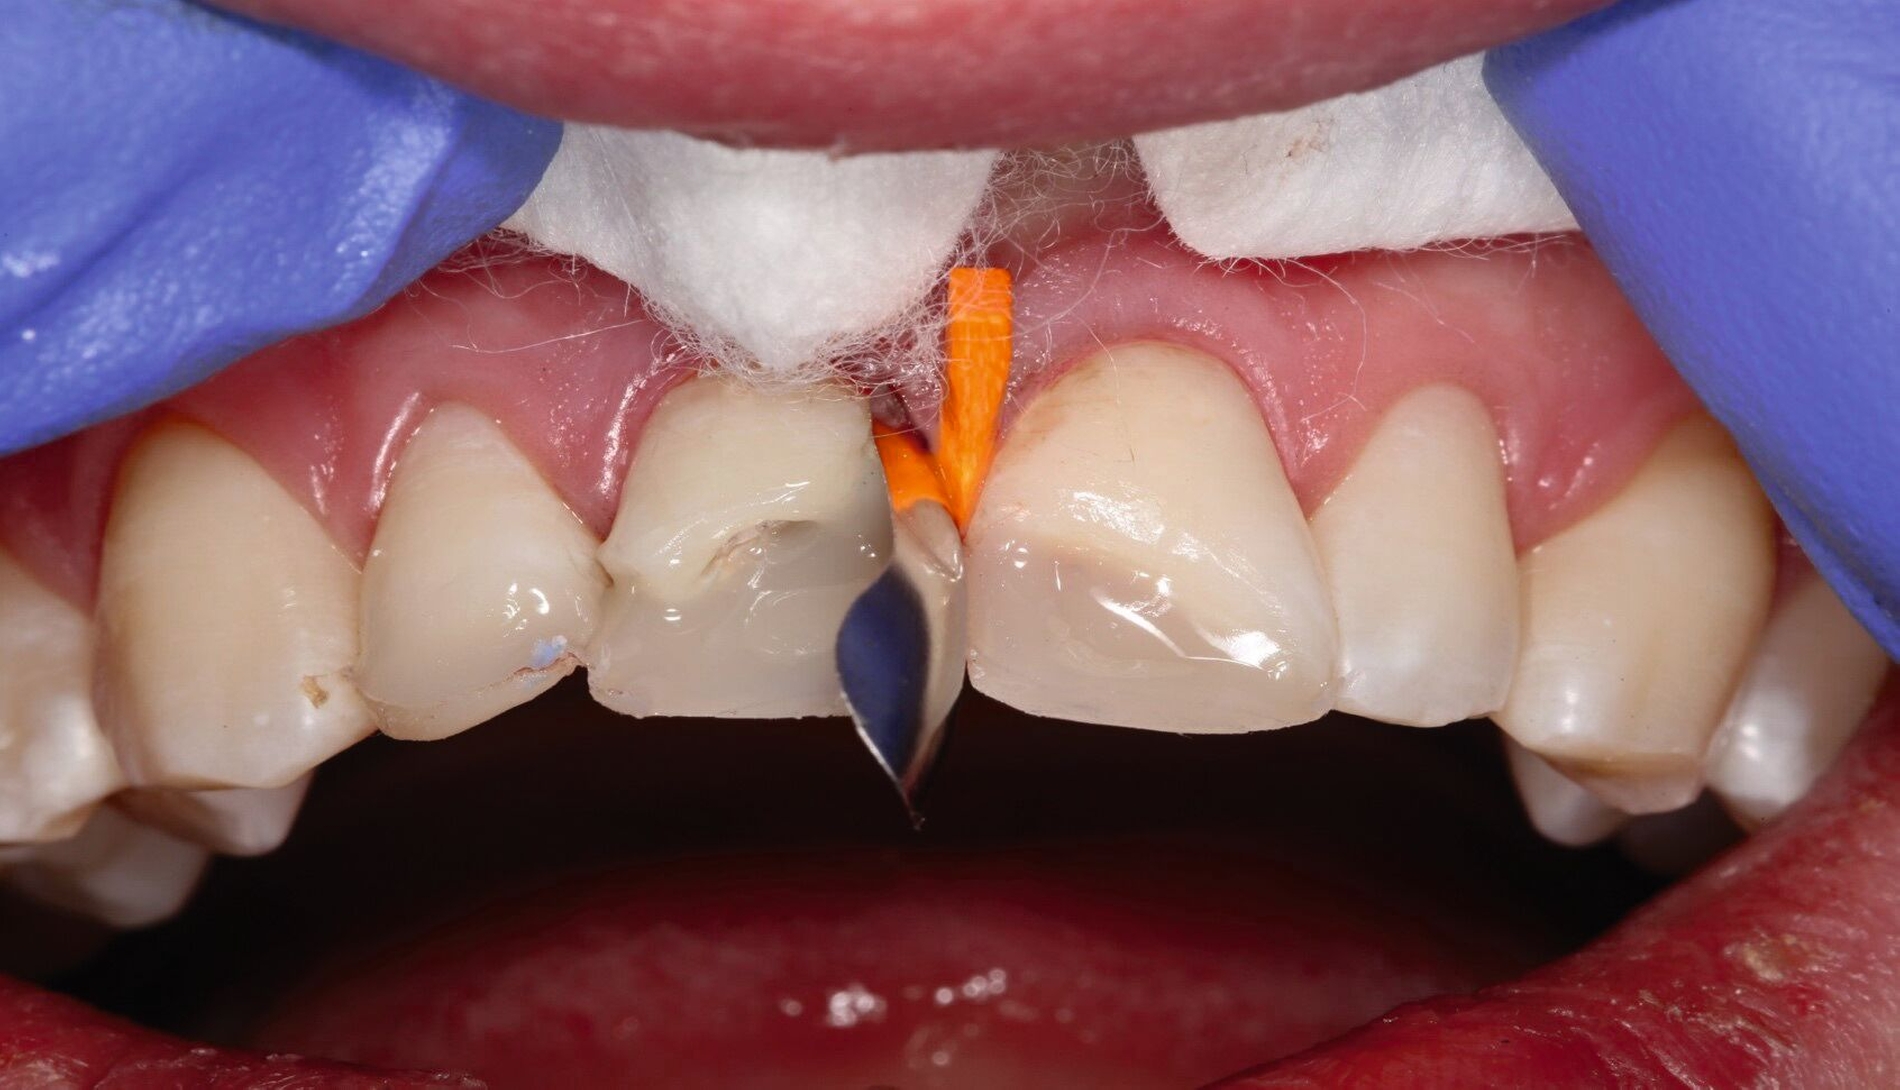

Im Rahmen der Notfallversorgung wurden die Dentinwunden an Zahn 12 provisorisch mit Glasionomerzement verschlossen und die Zähne 11 und 21 mit Kalziumhydroxid-Präparaten direkt überkappt und anschließend dentinadhäsiv versiegelt. Im Verlauf wurde ein Wax-Up für direkte provisorische Kompositaufbauten hergestellt (Abbildung 4). Zur semipermanenten Versorgung musste per Elektrotom mesial und palatinal an Zahn 11 Gingiva exzidiert werden, um einen adäquaten Zugang und eine suffiziente Kontrolle des Arbeitsfeldes zu gewährleisten (Abbildung 5). Durch die direkte provisorische Restauration war der Patient sofort versorgt. Er konnte ohne größere Beeinträchtigung am sozialen Leben teilnehmen und hatte so Zeit für die endgültige Therapieentscheidung (Abbildungen 6 bis 8).